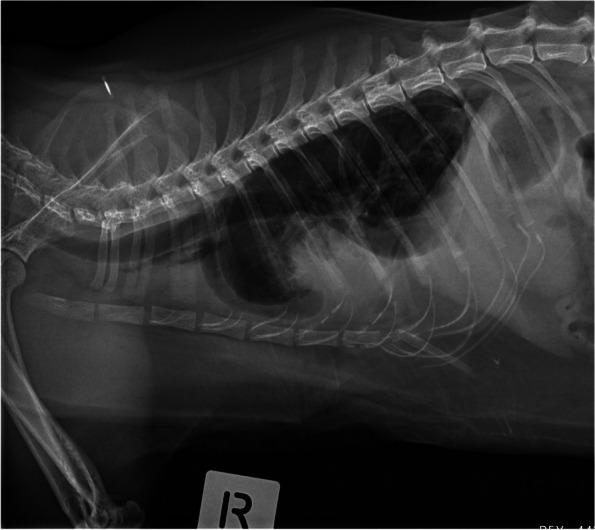

Data from 148 cats with pleural effusion and diagnosed with known aetiologies were retrospectively analysed. Sixty one cats had thoracic radiographs evaluated by consensus through pre-defined radiographic signs by two radiologists blinded to the diagnoses.

Congestive heart failure (53.4%) was the most common diagnosis, followed by neoplasia (20.3%), pyothorax (10.8%), idiopathic chylous effusion (5.4%), feline infectious peritonitis (1.4%) and "other" or cats with multiple diagnoses (total 8.8%). Cats with an enlarged cardiac silhouette had a high positive predictive value of congestive heart failure (90%). Mediastinal masses (100%)and pulmonary masses (100%) were highly predictive of neoplastic disease. Pulmonary nodules (50%) were poorly predictive of neoplastic disease. The remainder of the radiographic variables were not informative predictors of underlying disease.

In our sample of cats, congestive heart failure was the most common cause of pleural effusion. Radiographically enlarged cardiac silhouette and presence of a mediastinal mass may be useful predictors of aetiology, however there are limitations to the use of radiography alone as a diagnostic tool.